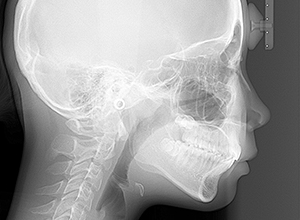

FP・IOP

X-Ray

X-Ray所見

セファロ所見 下顎骨はしっかりとしているが顎顔面の奥行きに比べて下顔面高さが低い。頭蓋に対して上顎骨は前方位にあり、上下顎骨の前後的位置関係のズレは大きかった。